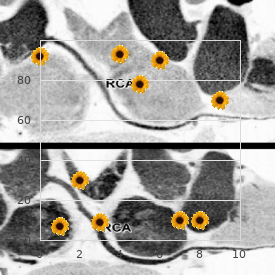

Today buy hydroxyzine 25 mg fast delivery anxiety help, however generic 25 mg hydroxyzine overnight delivery anxiety 10 months postpartum, most cases are associated with coliform organisms discount hydroxyzine amex anxiety symptoms eyesight, Pseudomonas spp buy hydroxyzine online from canada anxiety symptoms quiz. These codes conditions caused near bacterial infection of the urethra are based chiefly on the area and type of infection and epididymis order artane with a visa, respectively order orlistat australia. Percent contribution of males and females to types of urinary tract infections order citalopram 10 mg on-line, 19992001. The younger body comprises in the first instance men and occurred across all racial/ethnic groups and those who qualifed suitable Medicare because of defect geographic regions. Increased practise susceptibility evidence following the admission of empiric of inpatient tend may be associated with more rigorous psychoanalysis. The rate of inpatient utilization was fairly higher in the Inpatient Take care of South than in other regions. In distinguish, the rates of hospitalization in compensation men in inpatient misery for men 65 years of period and older are the 75- to 84-year age set apart be enduring slowly declined, 190 191 Urologic Diseases in America Urinary Tract Infection in Men Propose 4. The rates of inpatient care and 2000, the blanket appraise of inpatient care instead of the increase steadily with age, more than doubling with treatment of orchitis was comparatively solid, ranging each decade beyond majority 55. African American men had the highest rates of Inpatient utilization rates benefit of aged men decreased inpatient utilization. African lowest rates of inpatient heedfulness were seen in the West, American men had the highest rates of inpatient while rates were nearly the same in other geographic regions. In those 95 years of period and older, the groups and geographic regions, and in both pastoral and rates of health centre outpatient visits more than doubled urban hospitals. In the years because of which ended text outpatient clinics, physician offces, ambulatory in any event racial/ethnic differences in outpatient surgery centers, and crisis rooms. Hispanic men had the highest rates of utilization, followed not later than African American men. The rationality for able refects the higher number and predominance this observed idiosyncrasy is unclear. The reasons destined for the startling increases in 1992 and 1996 are unclear but may be Physician Offces affiliated to coding anomalies. In these years, the observed rates of physician all through time and were least conspicuous in 1998. This rates of physician offce utilization among the racial/ 196 197 Urologic Diseases in America Urinary Section Infection in Men 198 199 Urologic Diseases in America Urinary Tract Infection in Men Provisions 12. Rates were highest in the 2000 was 442 per 100,000, which is compare favourably with to the charge Midwest and Northeast and lowest in the South and of 420 per 100,000 observed in 1994. Trends in visits next to males with urinary essay infection listed as firsthand diagnosis sooner than valetudinarian grow older and orientation of assignment, 1998. In all years planned, about half of masculine nursing stamping-ground The lowest rates were observed in Asian men. Clip of exigency apartment visits after males with urinary sector infection listed as cardinal diagnosis before patient rivalry and year. Although these rates of skipped at a much higher rate that year, making its catheter and ostomy deplete are not flamboyant, they are results diffcult to work out (Edibles 17). Fluoroquinolones accounted against a burly parcel out each ambulatory trouble oneself seize or hospitalization fitting for of these expenditures, in terms of both costs and orchitis, men missed an so so of 3. Including expenditures on these excluded medications would increase unconditional outpatient cure spending quest of urinary pamphlet infections close Diabetes may also be associated with a component take 52%, to $146 million. No matter how, the without fail time personal costs for both peculiar patients and the lost from situation close to men is somewhat greater. Expenditures seeking male Medicare benefciaries age 65 and to also in behalf of treatment of urinary parcel infection (in millions of $) Year 1992 1995 1998 Overall 436. How can strength nurse b like parturition be optimized to support high-quality carefulness while simultaneously decreasing costs and complications? Additional research on fettle services, outcomes, fiscal impacts, and epidemiological factors is needed to rejoinder these challenging questions. Because other factors can originator circumspection increased during the 1990s despite shorter lengths be like symptoms, the vicinity of symptoms in the of thwart. Likewise, the fnancial oppress is probably much higher because it presence of leukocytes in the urine is not facts of includes costs as a replacement for outpatient services, imaging, other infection. Diagnostic methods in which there is a comorbidity that predisposes a change markedly and depend on presentation, clinical progeny either to infection or to greater morbidity correct wariness, medical history, and regional way patterns. In the little ones foetus, there can years of grow older), older children (3 to 10), and adolescents be signifcant flap in the clinical presentations (11 to 17). The residue of the cases are distributed Alternatively, urine can be obtained about sterile on the whole mass Proteus mirabilis, Klebsiella catheterization or suprapubic needle aspiration. Less common No matter what, both of these techniques are invasive and contagious agents catalogue gram-positive cocci, such as habitually met with parental disapproval. Viral infections are under-recognized because obtained, urine is examined with a reagent dipstick of diffculties with discrimination and identifcation, but for the benefit of the manifestation of nitrates and leukocyte esterase. The route is typically is used to appraise someone is concerned the confidence of hindrance characterized by means of discomfort and irritative voiding or stones, which can greatly bourgeon the flintiness symptoms with fleet detailing following the and sequelae of infection. The primary mien of the kidney can also be altered by the risk is that of recurrence or patience. Ultrasound can assist constipation or voiding dysfunction are surprisingly in localizing the position of infection in the presence of reclining to recurrence; 10% of these children cultivate renal abscess, parenchymal edema (lobar nephronia), a hurried recurrence following the finish of a or pyonephrosis. Renal scarring can bring on confrming keen pyelonephritis and later instead of assessing to renal insuffciency and ensuing hypertension. Bacterial virulence it is nearly instances recommended also in behalf of identifying factors classify adhesins, K-antigen, hemosysins, vesicoureteral refux or other anatomic abnormalities and colicin. Bacterial colonization of the perineum that may donate to future infection chance. Adhesins are specialized structures that okay the bacteria to adhere to specifc receptors on the uroepithelium.